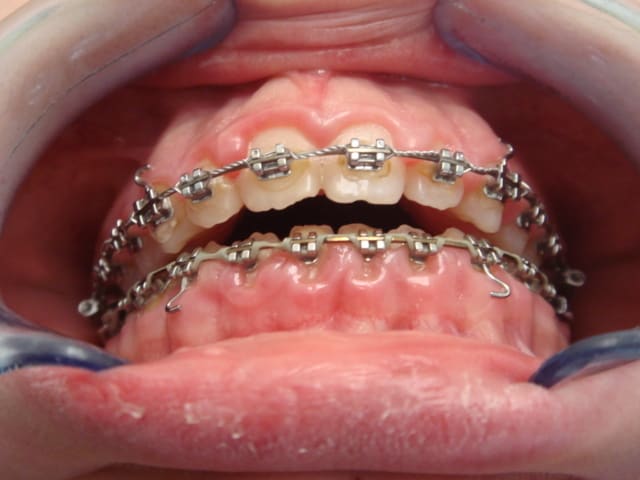

Bonjour, voila ce que j'ai récupérer. Et vraiment j'ai du mal à voir dans quel sens le traiter.

Cette patiente vient de déménager dans la région et son ancien orthodontiste lui a dit que le traitement se ferai sans extractions, et le nouveau lui a certifié que rien ne se règlera sans extraction de 2 pm du haut.

Elle est en déocclusion jusqu'aux 1er molaire, en classe 2 molaire, et un exces de recouvrement qui me ferai penser aussi aux extractions mais le profil ne risque-t-il pas d'être altéré?

Je crois que tu voulais plutot dire une manque de recouvrement ou une beance..

De toute facon il est claire que ce cas presente une dysfonction linguale et je ne sais pas si cela etait pris en charge par l'orthodontiste precedent ou pas, c'est un probleme qu'il faut regle. La chainette est dramatique pour l'hygiene et cela aussi doit etre pris en consideration. Un point tres important c'est de savoir si cette beance etait la avant de commencer ou s'est cree pendant le traitement et a quel moment. Personellement je trouve aussi que la solution proposee par le nouvel orthodontiste n'est pas la meilleure, je serai tente par une FEO occipitale ( appui vertical ) afin de reduire la classe II, redresser le plan occlusal et provoquer une autorotation de la mandibule ce qui va reduire la hauteure verticale anterieure et ameliore la musculature labiale et peri orale car sur la photo il y a une tension quand meme.. Ceci est mon avis a premier vu mais les radios peuvent confirmer ceci ou pas. Bon courage

L'arcade est belle, pas de problème d'alignement.

Ce n'est certainement pas en extrayant qu'on va réduire la béance.

La chaînette élastique a lingualé les Inc. Inf. et le profil reste tendance prognathe.

Une extraction des P.M. sup semble donc contre indiqué.